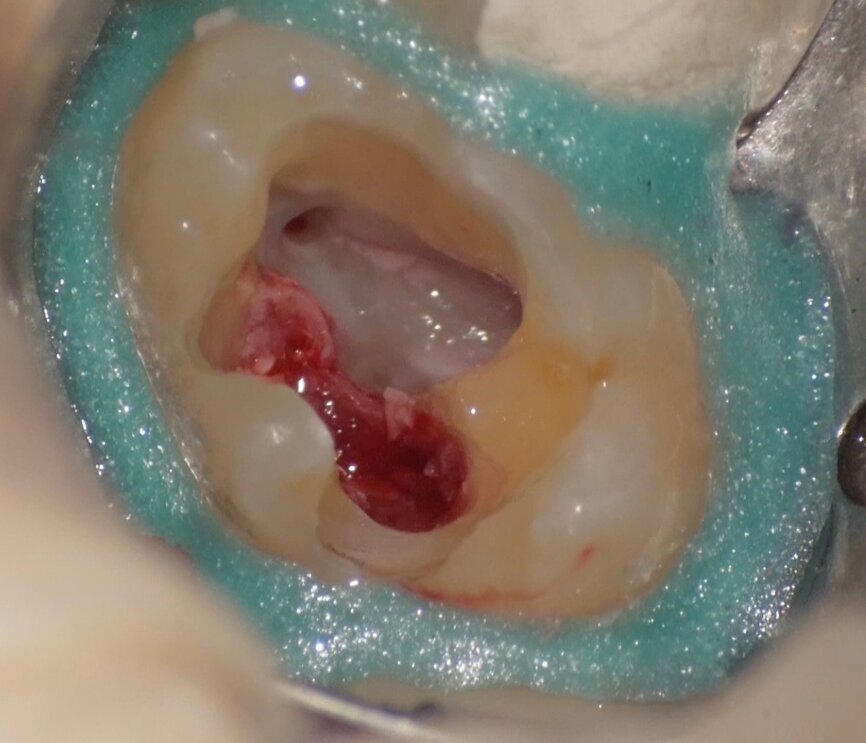

Comparing the two teeth shown in Figures 10 to 22 demonstrates just how important it is to analyse all the slices of the CBCT study correctly. We can see that, in the maxillary molar, the lesion penetrates into the pulp chamber, starting from the root’s distal surface, but remains within the coronal third of the tooth, without significantly affecting the integrity of the pulp chamber floor (Figs. 10–15). The clinical images illustrate the operative treatment phases, from resorption debridement through to repair using bioceramic cement (Figs. 16–19). The final radiographic images confirm the validity of the conservative and endodontic treatment of the tooth. The situation is completely different for the mandibular molar, where the evaluation of the CBCT scan clearly reveals the extent of the resorption, which invades the pulp chamber floor until the furcation, a situation that cannot be determined from observing the preoperative radiograph alone (Figs. 20–22).